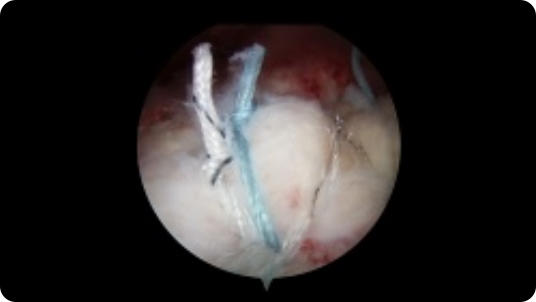

Arthroscopic image of an ACL tear Arthroscopic image of an ACL reconstruction

ACL Reconstruction